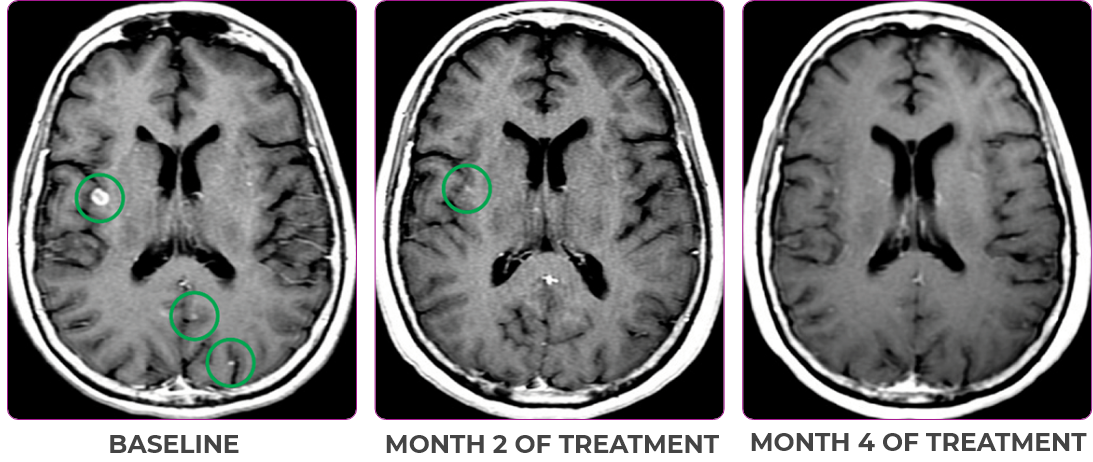

Response in primary and metastatic lesions1

MRIa imagery of the brain. Green circles indicate baseline brain metastases.1

SCAN 2: BRAIN

aMRI, magnetic resonance imaging.

- Partial response to treatment that was confirmed at 2 months (34% tumor reduction)

- Patient remains on VITRAKVI after more than 4 months of treatment